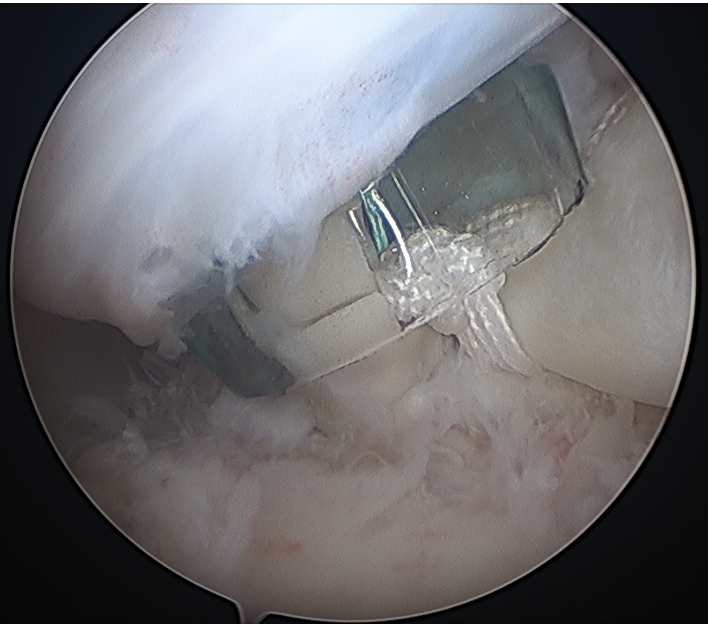

Portal just anterior to supraspinatus tendon

Tag biceps and release

Anchor biceps tendon into bicipital groove